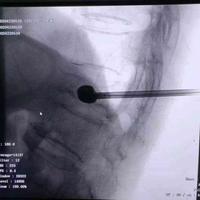

支架撑开并保留的椎体成型

支架撑开并保留的椎体成型...

由 medjpg 发表于 2026-03-24 22:32